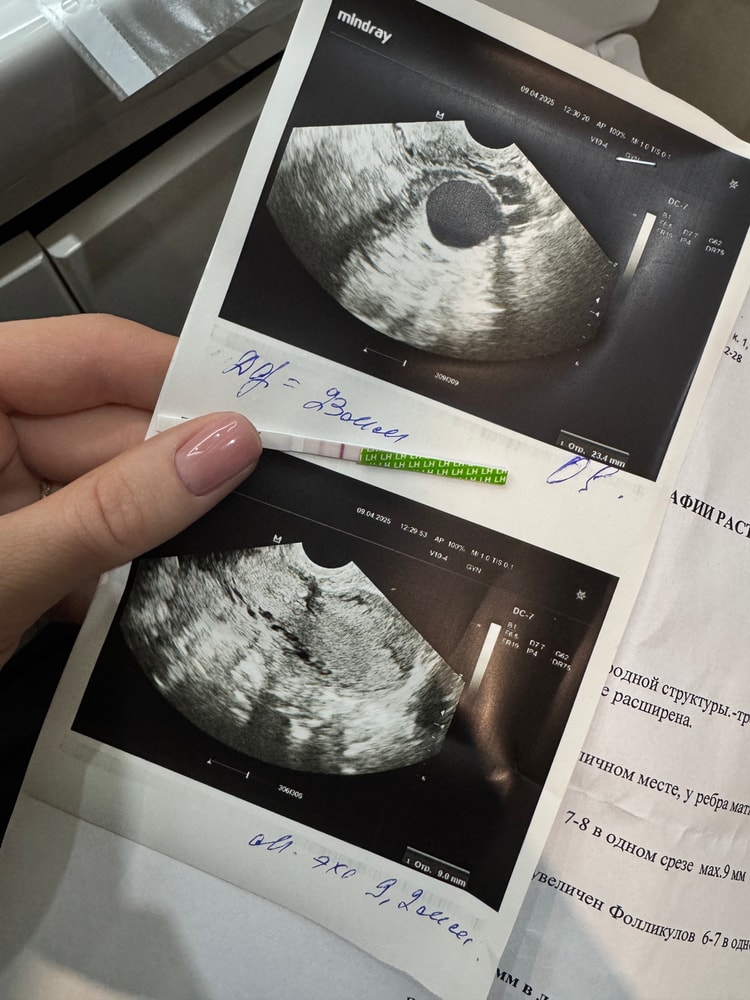

16дц - ДФ 23, симптомов нет, тест на О отрицательный

Я очень расстроена, сходила еще раз на фолликулометрию (16дц) а мой фолликул еще не лопнул, уже 23мм. Врач говорит «такой хорошенький, как будто вот вот лопнет сего

Сбегала сегодня на узишку. 13 дц. Доминантный фолликул 19,8мм, эндик 9,5 трех слойный ; регрессирующее ЖТ в другом яичнике с прошлого цикла 10мм. Тесты на О пока отрицательные. Вот думаю, когда лучше ПА 🤪